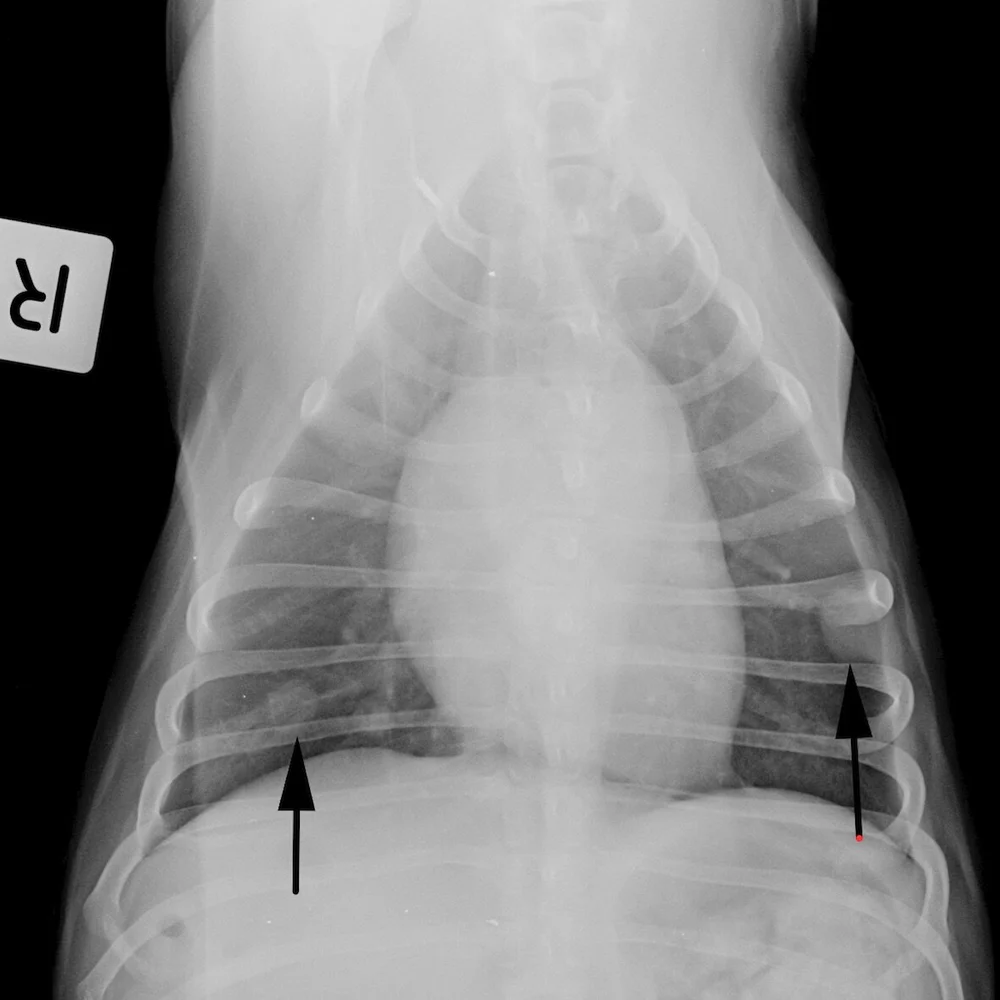

In cases of bone cancer, the affected bone tissue will show areas of destroyed bone and others with bone proliferation;

Without treatment, a dog diagnosed with osteosarcoma will succumb to the cancer in only one to two months. In cases of bone cancer, the affected bone tissue will show areas of destroyed bone and others with bone proliferation; While the prognosis can be discouraging to say the least, there are options available that can extend the it's sad to say, but dogs with bone cancer do not have a very long life expectancy, especially if the cancer has metastasized. Bone cancer in cats and dogs usually means surgery and chemotherapy. A body is made up of trillions of cells, the building blocks of all also read: